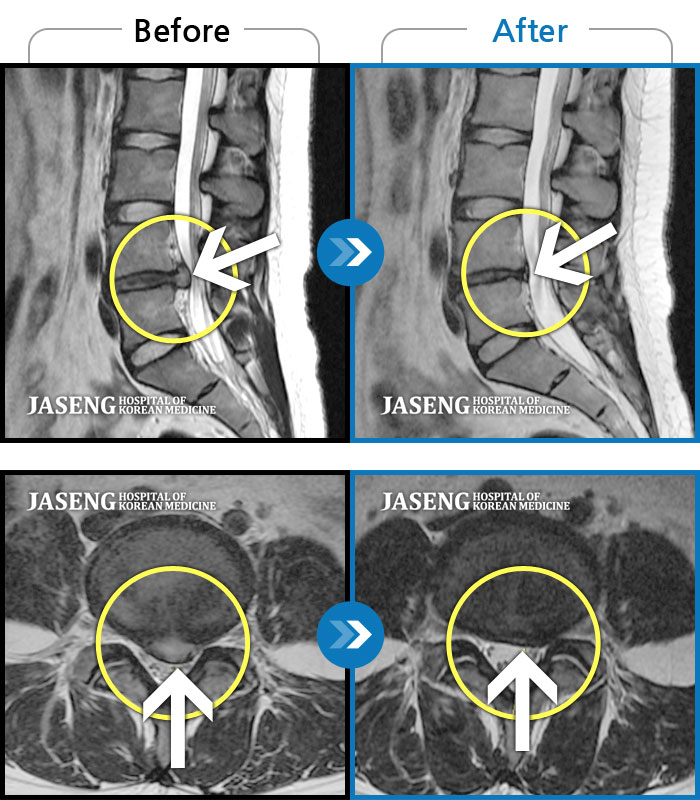

병원에 도착하여 각종 검사하고 담당의사(이병휘 원장님) 영상사진에 의한 디스크 관련 상세한 설명과 상담, 약물치료를 병행한 진료관련 향후 계획 등 설명을 들고 귀가하였습니다. 당장 입원하여 허리안정이 중요한데 직장업무관계로 주말을 이용하여 4일간 입원하였고, 퇴원하여 2014년 1월말까지 주 2회 정도 내원하여 약물치료를 병행하였습니다. 치료기간 중 주3회 정도 1시간 정도 걷기 운동하였고, 매 시간 마다 10분 정도 양손을 허리에 손을 올려 좌우로 움직이다가 호전되어가는 증상에 조금씩 허리돌리기를 하였습니다. 진료 후 약 3개월부터 5개월까지 2-3주 단위로 내원하여 침을 맞고 꾸준하게 신체운동을 병행하였습니다.